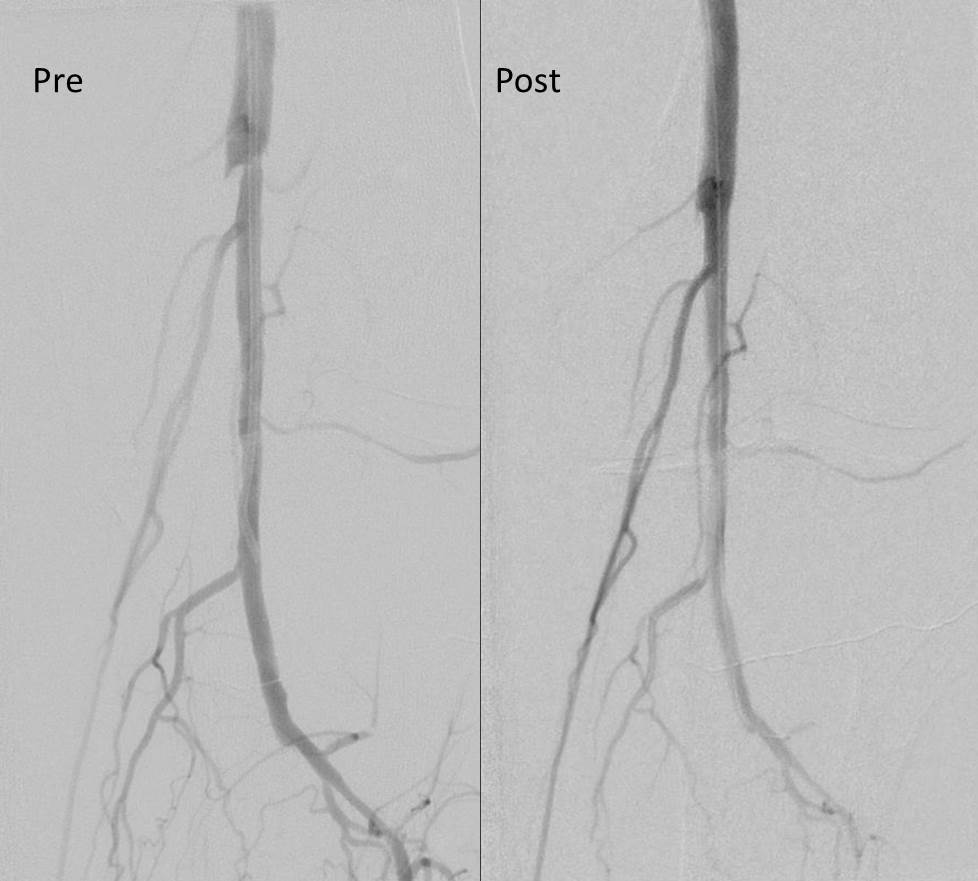

The patient came back in followup -it has been 4 years since his infection was repaired. He was complaining of short distance claudication. His wound healed well and remains closed. CTA shows along with his short segment SFA occlusion which we will treat, a widely patent R. EIA (below).

The remote endarterectomy of the external iliac artery remains patent. Compare this to the preop CTA which I found and wasn’t available when I posted this case originally:

The chronically occluded EIA can be readily seen. The artery shown in the current CTA is that recanalized artery.